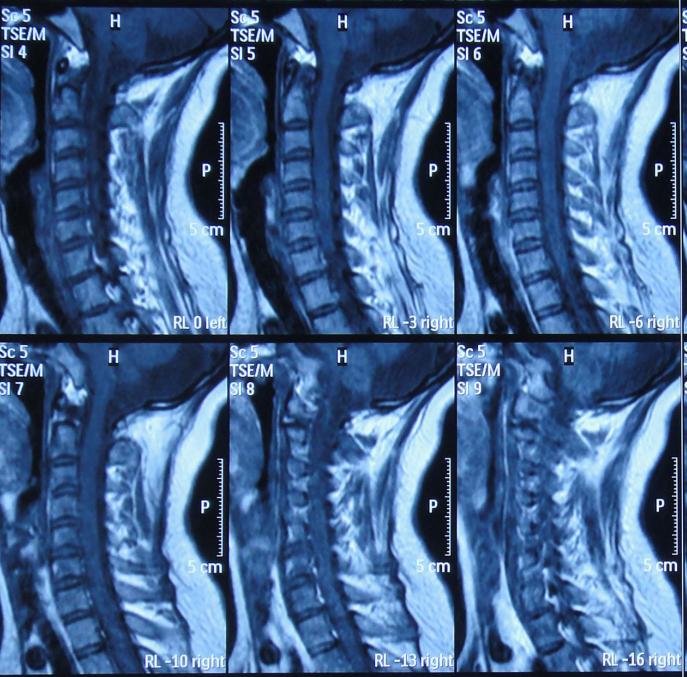

第1家医院治疗12天后即2015年8月15日,因仍头痛,考虑跟颈椎有关但查核磁后未见明显异常(图-3)。

图-3:2015年8月15日颈椎MRI